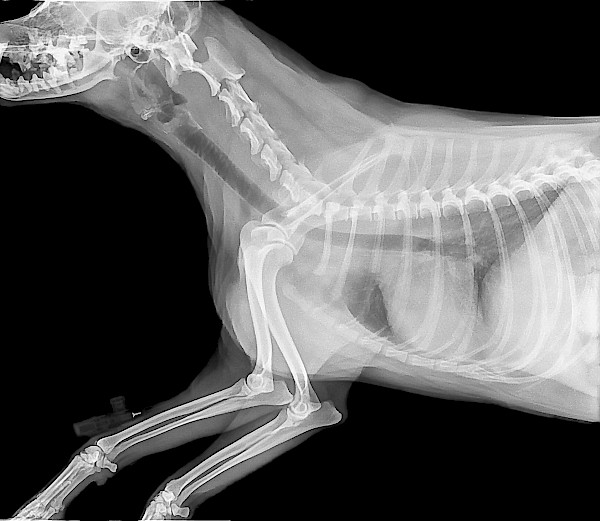

- Artritis: Artritis je pogosto stanje pri starejših psih, vendar lahko prizadene tudi mlajše pse. Simptomi lahko vključujejo okorelost, šepanje in težave pri vstajanju ali hoji. Možnosti zdravljenja vključujejo zdravila, uravnavanje telesne teže in fizikalno terapijo.

- Osteoartritis: Osteoartritis je degenerativna bolezen sklepov, ki lahko pri psih povzroči bolečino, okorelost in omejeno gibljivost. Čeprav obstajajo zdravljenja, ki lahko pomagajo pri obvladovanju simptomov, zdravila za osteoartritis ni. Psi s tem stanjem lahko potrebujejo vseživljenjska zdravila, dodatke in fizikalno terapijo za obvladovanje simptomov.